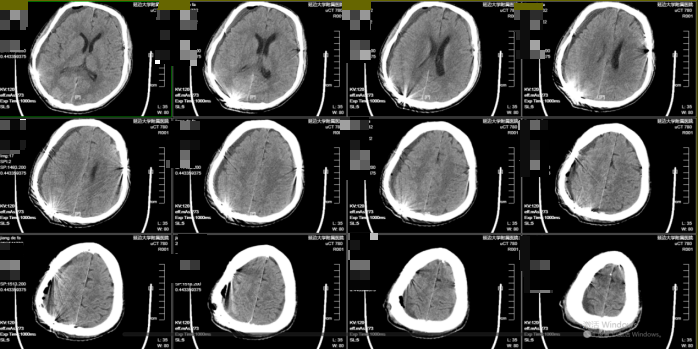

考虑患者高龄、基础状态差,特别是既往肝癌手术(影响凝血因子合成)及脾脏切除(可导致血小板计数及功能异常)导致的凝血功能紊乱,保守治疗风险极高且效果较差。黄宪主任医师、马吉男主治医师团队果断行右侧颅骨钻孔引流术(左侧给予保守治疗),术后瞳孔回缩,意识转清。术后密切监测病情变化。考虑其脾切除后存在凝血机制异常,血肿复发概率高,与家属沟通后进一步行经导管双侧脑膜中动脉(MMA)栓塞术,从而降低复发率。术后神清语明,四肢无瘫,顺利出院。1个月后复查头部CT右侧慢性硬膜下血肿明显减少,左侧慢性硬膜下血肿基本吸收。四肢肢体肌力V级。事实证明,经导管双侧脑膜中动脉(MMA)栓塞术治疗慢性硬膜下血肿效果显著,且依据文献报道可将复发率降至5%以下。

图4、1个月后复查头部CT

65岁男性患者,头痛头晕伴右侧肢体活动不灵约3天。头部CT示双侧额顶部慢性硬膜下血肿。黄宪主任医师、马吉男主治医师团队先行经导管脑膜中动脉(MMA)栓塞术,术中造影显示异常增生血管消失。接台行双侧颅骨钻孔引流术,术中见血肿量明显减少。术后恢复顺利,头痛消失,肌力改善,随访当地医院头部CT示无复发。